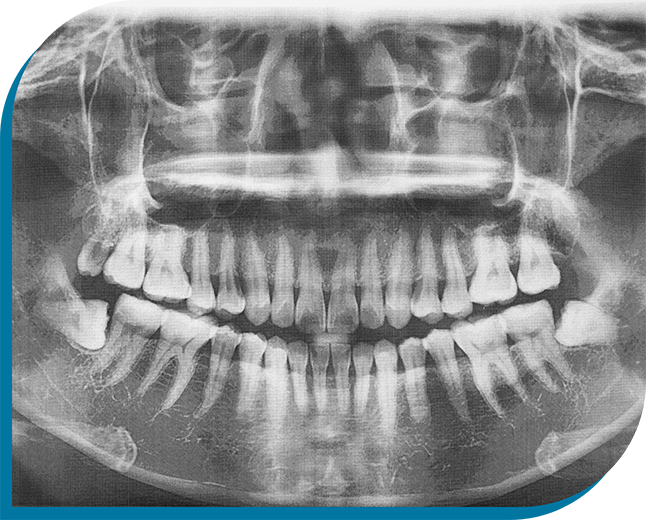

Removing wisdom teeth is often considered a rite of passage for many young people. Their eruption or lack thereof can cause pain because of abnormal growth. They can also be difficult to clean, which increases the risk of cavities and gum disease. Dr. Uldrikson’s decades of experience allow him to complete wisdom tooth extractions in Kingman with assurance and ease, effectively creating space for a healthier smile. Have wisdom teeth that need to be removed? Schedule an appointment today.

You’ll receive local anesthesia to numb your mouth, and you can also get sedation if you need extra help staying relaxed. If your wisdom teeth have partially erupted and are visible above the gumline, Dr. Uldrikson will extract them like he would any other tooth, moving them back and forth until they just slip out.

If you have impacted wisdom teeth, a more complex procedure will be required. He will need to place a small incision in the gums and remove a small amount of bone to reveal the underlying teeth. Depending on their positions, he may also need to section each tooth into pieces for easier removal.